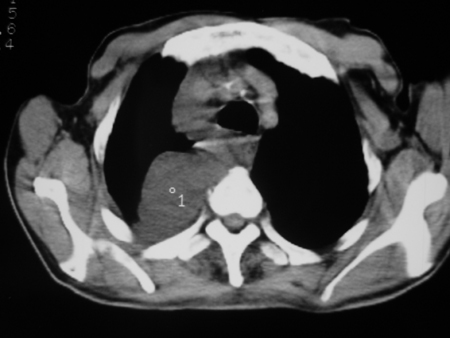

男77岁,胸痛就诊

右侧胸腔积液,部分包裹,右下肺膨胀不全,右下肺感染。

考虑右肺门占位并下叶不张 右胸包裹积液

右肺中叶及下叶炎症并胸腔积液(部分包裹),建议抽液后复查ct除外占位。

右侧胸腔积液,部分包裹,右下肺膨胀不全,右下肺感染